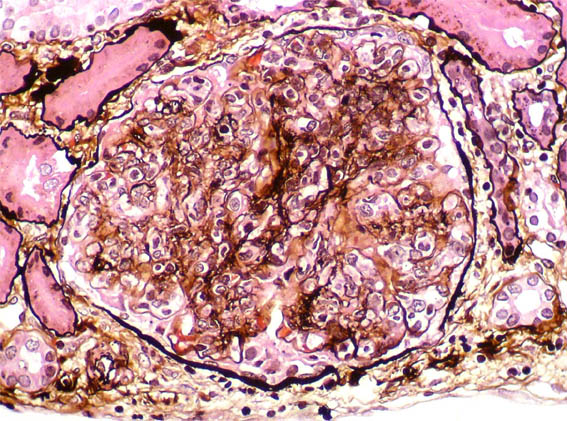

Figure 7. Methenamina-silver stain, X400.